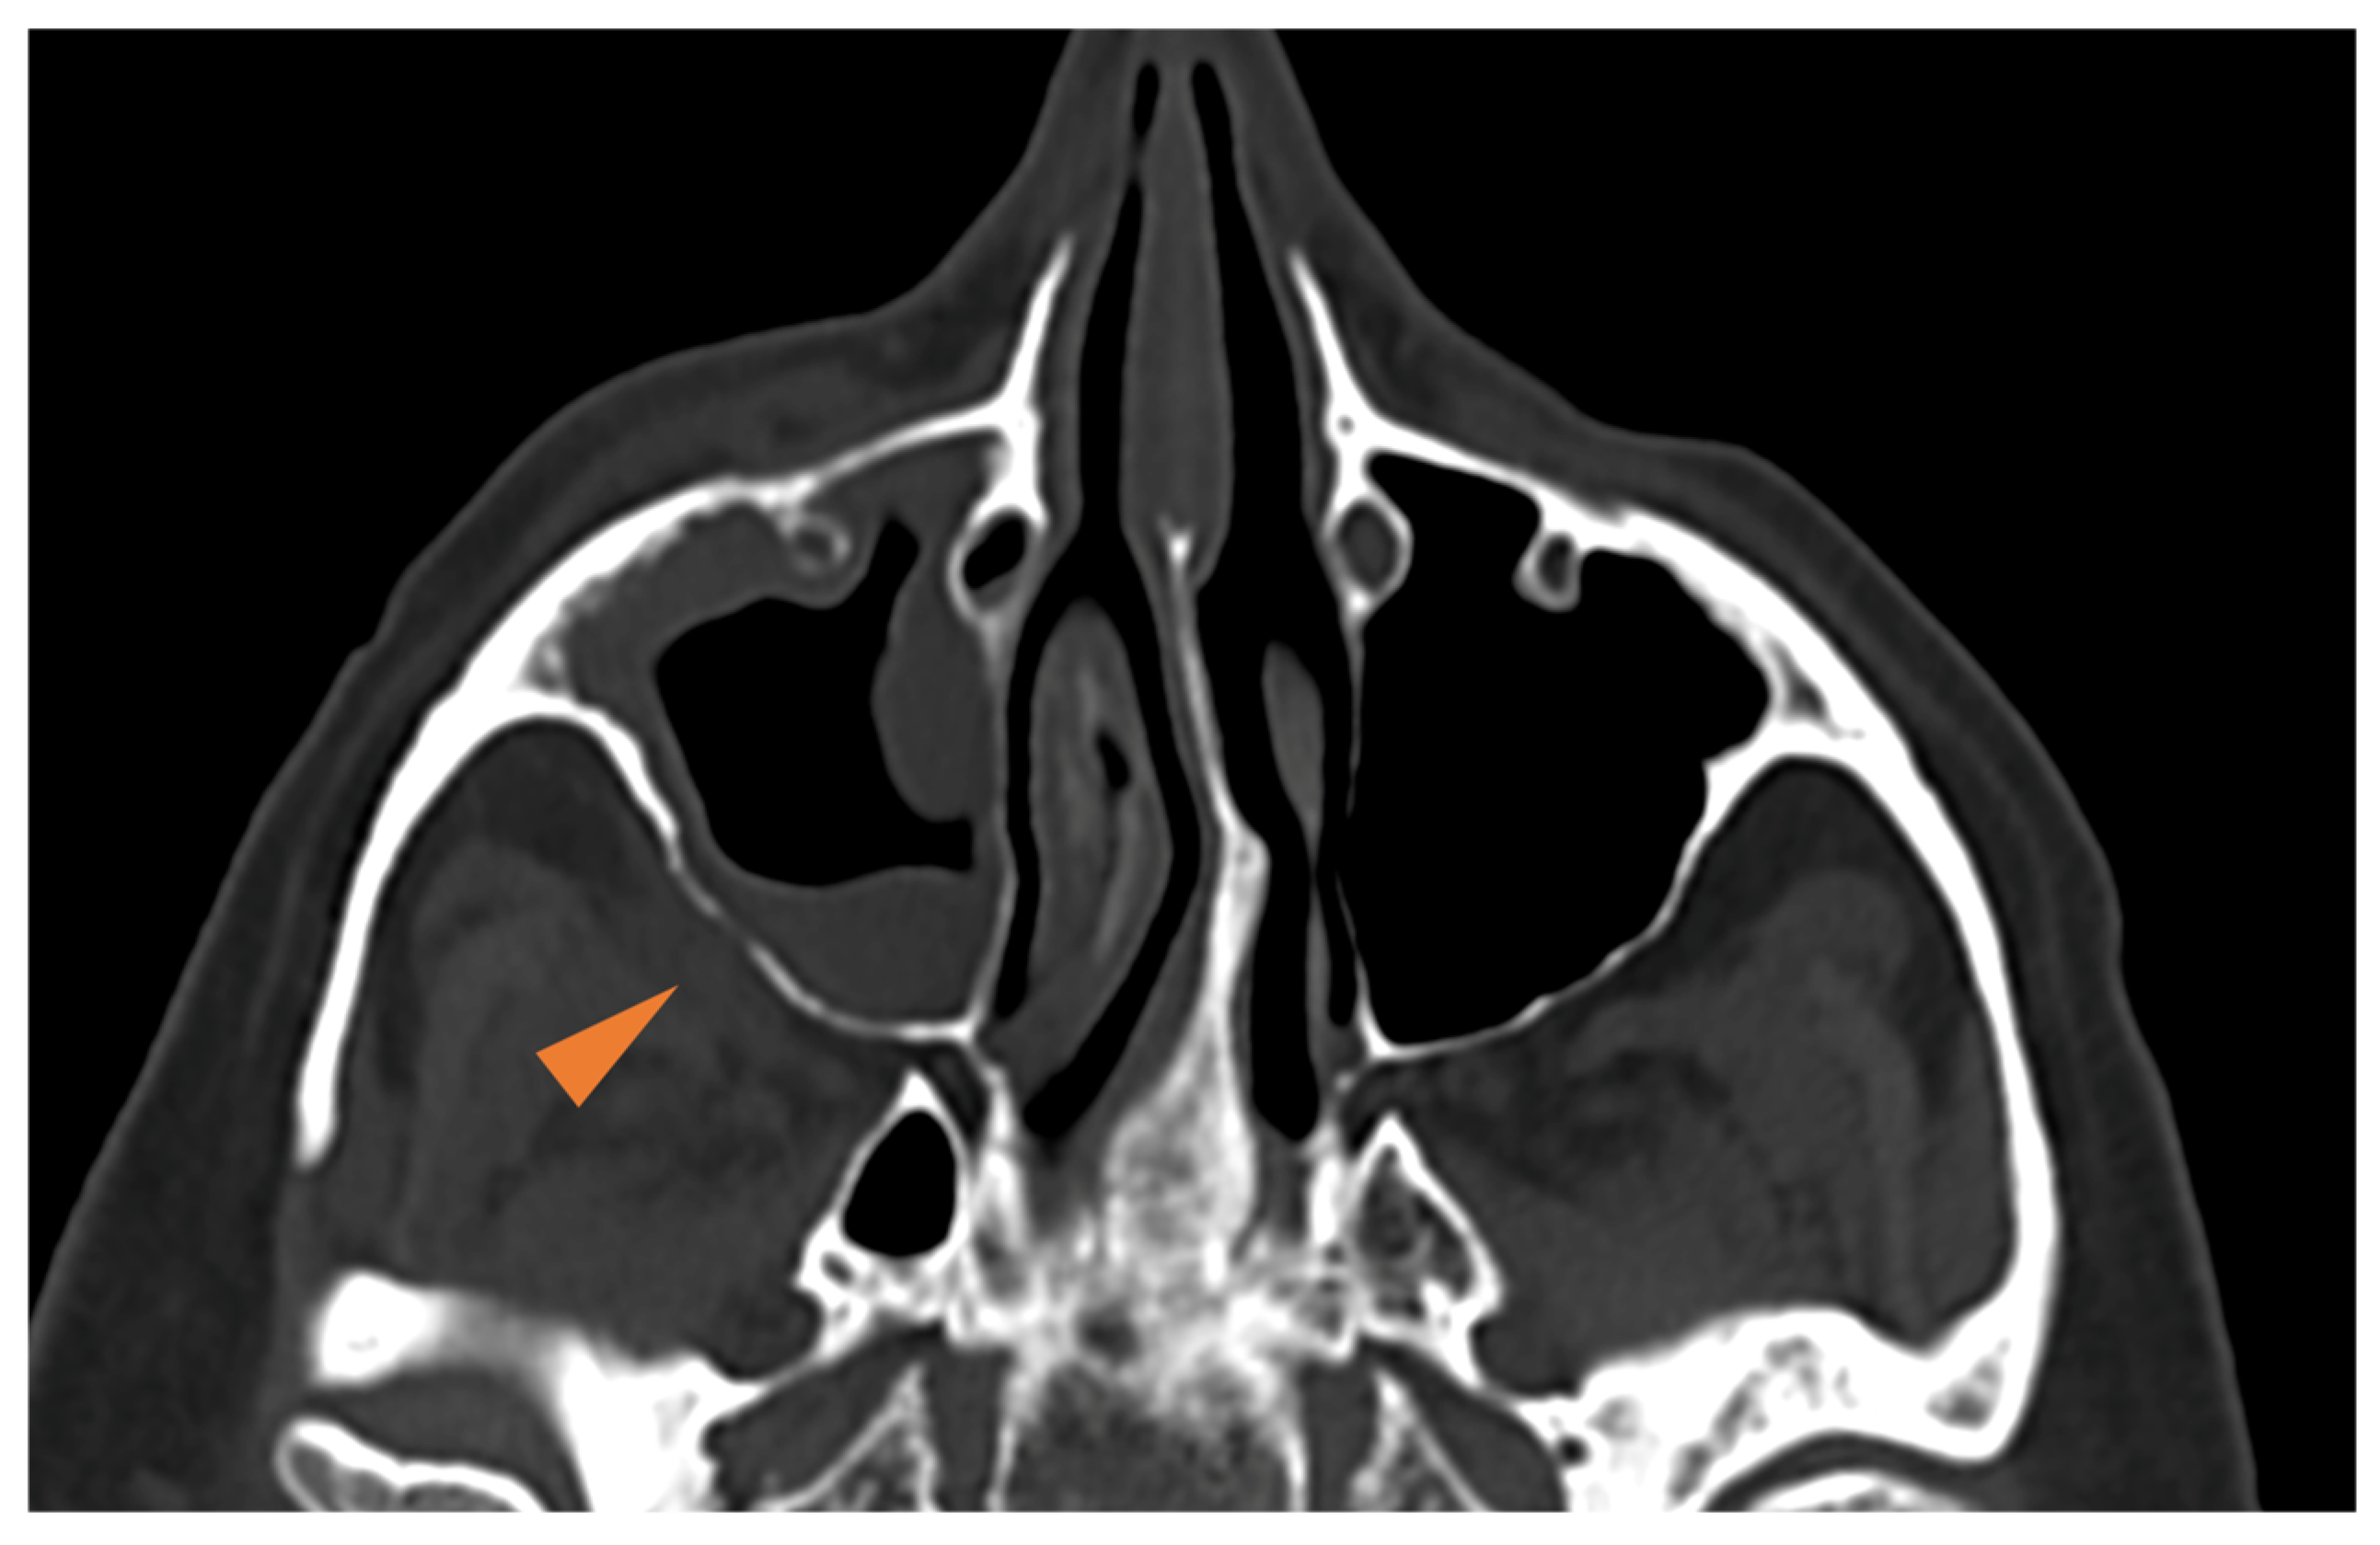

- Middlebrooks, E.H.; Frost, C.J.; De Jesus, R.O.; Massini, T.C.; Schmalfuss, I.M.; Mancuso, A.A. Acute Invasive Fungal Rhinosinusitis: A Comprehensive Update of CT Findings and Design of an Effective Diagnostic Imaging Model. AJNR Am. J. Neuroradiol. 2015, 36, 1529–1535. [Google Scholar] [CrossRef] [PubMed]

- Silverman, C.S.; Mancuso, A.A. Periantral soft-tissue infiltration and its relevance to the early detection of invasive fungal sinusitis: CT and MR findings. AJNR Am. J. Neuroradiol. 1998, 19, 321–325. [Google Scholar] [PubMed]